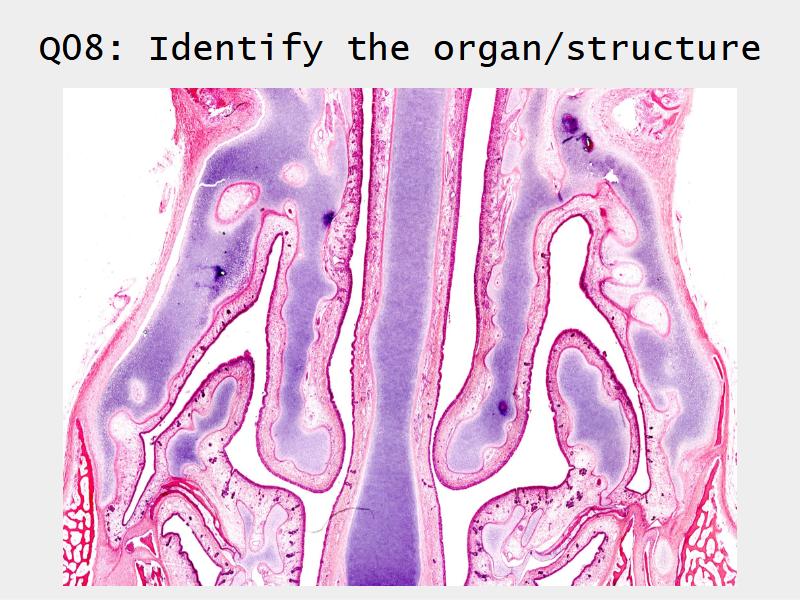

Slides: Respiratory System

- Slide 71: Nostril

- Slide 108: Olfactory epithelium

Olfactory epithelium